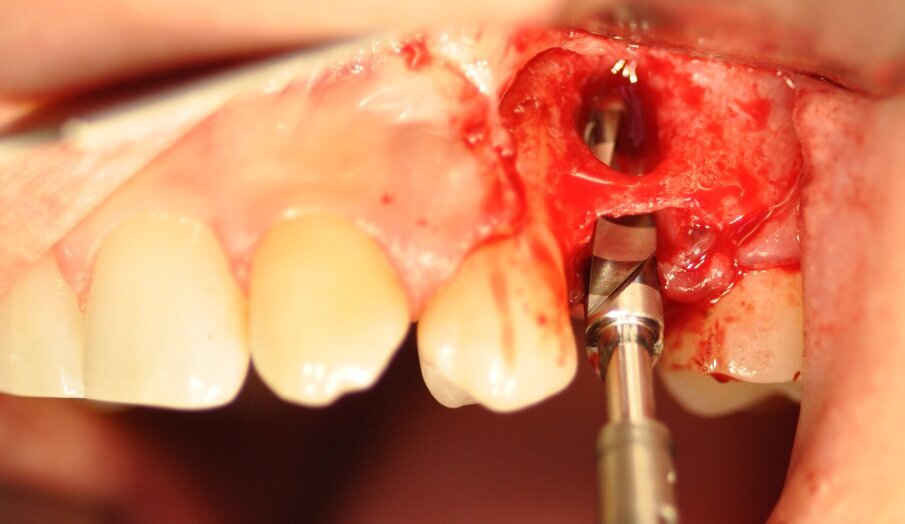

La paziente presentava un primo premolare superiore sinistro non recuperabile. La CBCT mostra la situazione iniziale (Fig. 1). Si noti quella che appare come una grande fenestrazione buccale nell’area della resezione radicolare (Fig. 2). Il dente fratturato è stato estratto (Figg. 3, 4). Lo scollamento del lembo di accesso rivela la fenestrazione buccale (Fig. 5). L’osteotomia è stata preparata secondo il protocollo di fresatura di Neoss ProActive Edge (Fig. 6). Successivamente viene posizionato un impianto Neoss ProActive Edge Ø 5.0 × 13 mm (Fig. 7). L’impianto è stato posizionato in una situazione di disponibilità ossea molto limitata e densità ossea media (Fig. 8). Nonostante le limitazioni dovute alla condizione ossea, è stata raggiunta una buona stabilità primaria. È stato utilizzato un torque di inserimento di 20 Ncm, l’ISQ è risultato in un range di 70/77. Per correggere la fenestrazione buccale è stato eseguito un innesto con particolato osseo di origine porcina (Fig. 9). L’innesto osseo è stato coperto con una membrana di collagene riassorbibile (Fig. 10). Il lembo mucoso è stato suturato attorno al pilastro di guarigione in PEEK, consentendo la guarigione in una sola fase (Fig. 11).